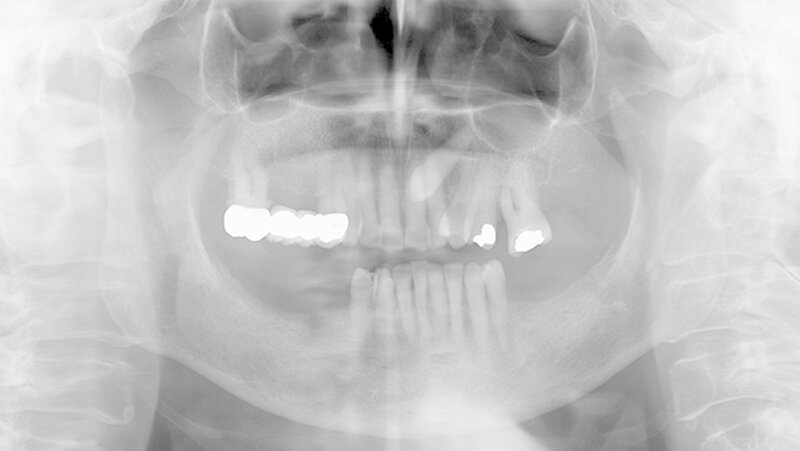

Aufgrund der schmerzhaften Gingivitis hatte die Patientin zudem Probleme mit der Nahrungsaufnahme. In der Panoramaschichtaufnahme (Abbildung 2) zeigt sich neben einem impaktierten Eckzahn ein Furkationsbefall der Molaren mit Konkrementen sowie ein altersentsprechender, generalisierter horizontaler Knochenabbau. Dennoch erschien uns das Volumen der Gingiva nach bereits erfolgter geschlossener Parodontaltherapie ungewöhnlich.